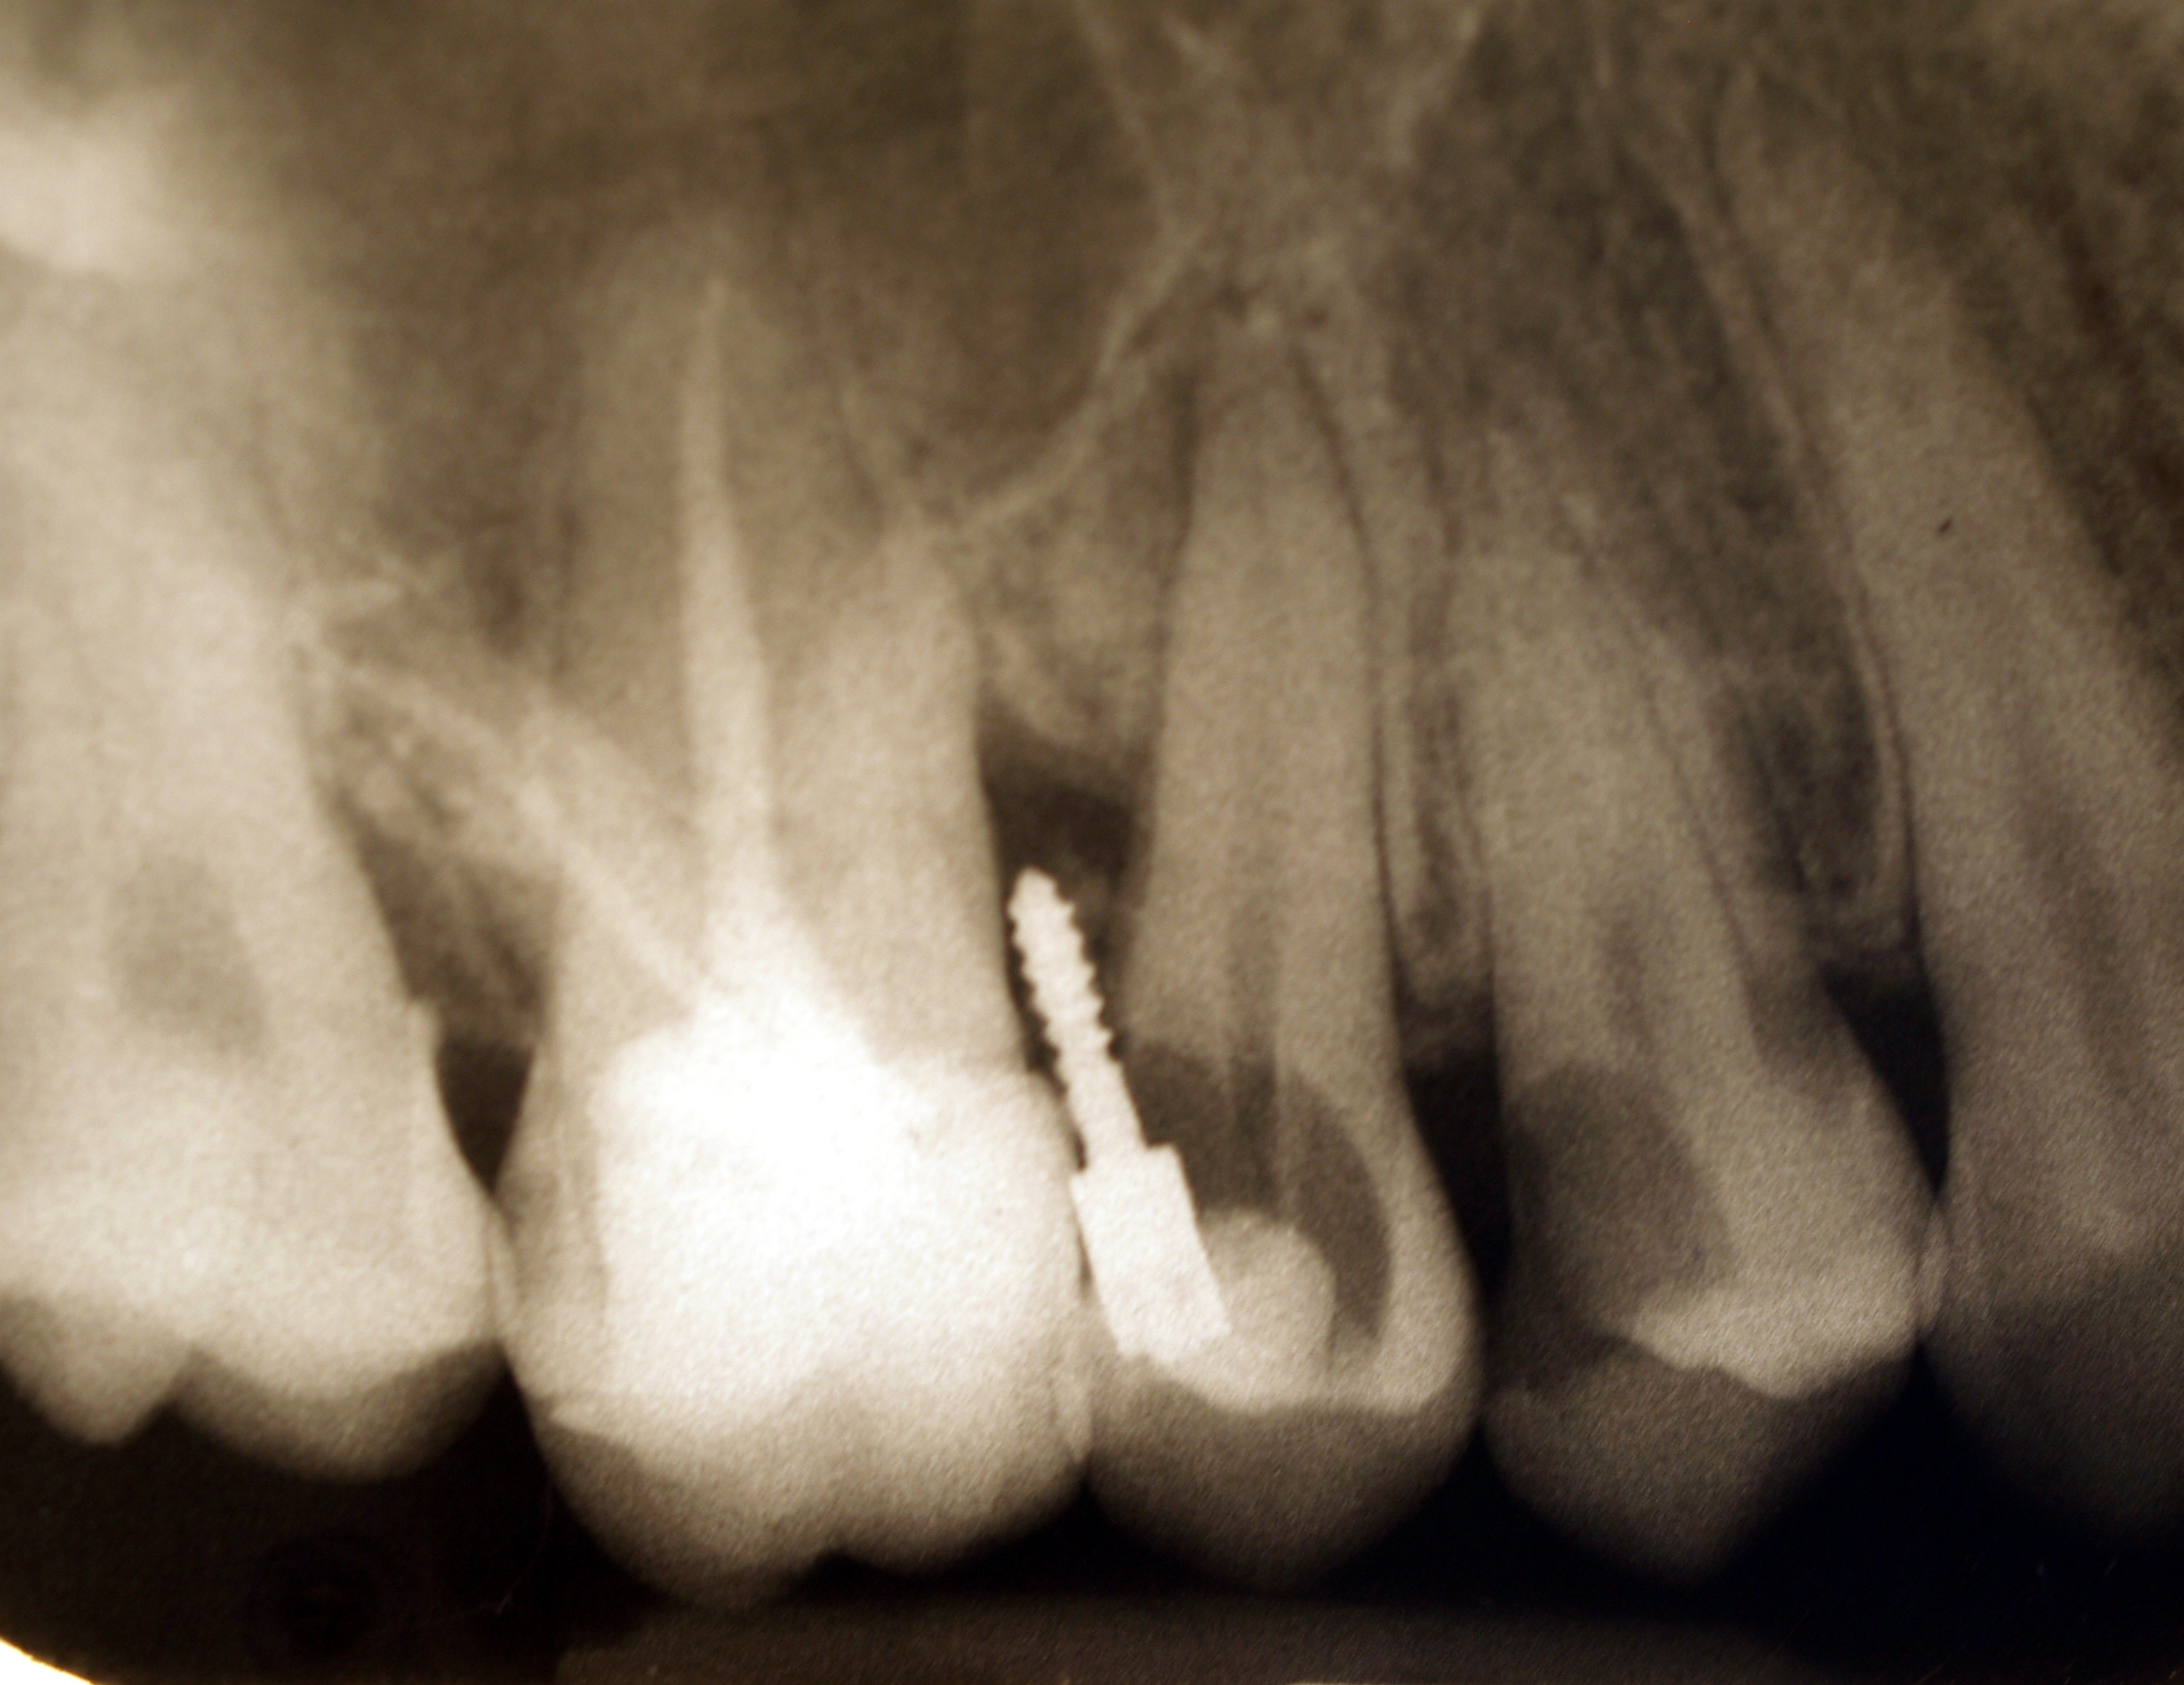

Naprawa i usuwanie wkładów koronowo-korzeniowych - galeria